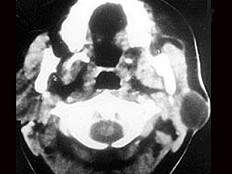

女性,30岁,右侧腮腺无痛性包块5个月,无面瘫,触诊肿块质韧,表面光滑。大小约6×8厘米,B超示腮腺浅叶实性肿块 ,均质,包膜完整。患者相片及影像资料见下图。

8.患者应该诊断为  (    )

9.患者的最佳手术方式是  (    )

10.手术中若以下颌缘支寻找面神经主干,其主要标志是  (    )

正确答案:8.B;9.B;10.A